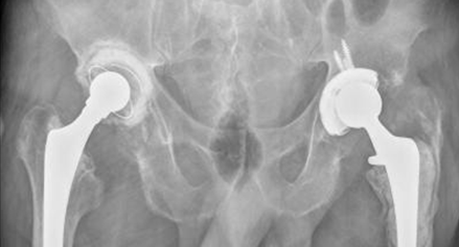

Fig 117. Cadera Post-quirúrgica.

Rx AP. Hemiartroplastia unipolar en el lado derecho y bipolar en el izquierdo.